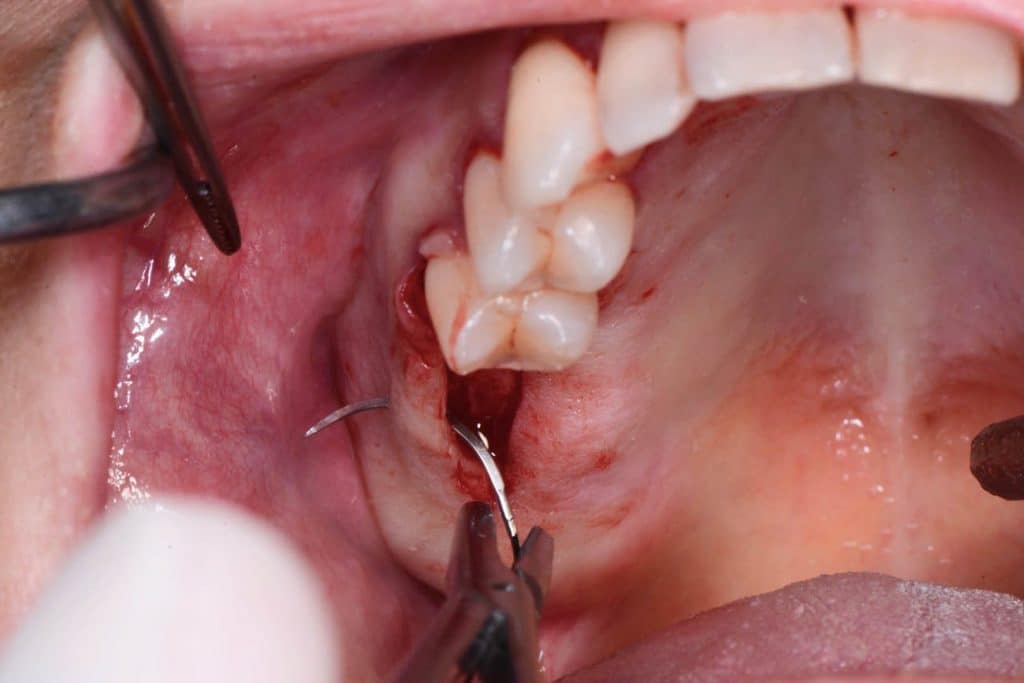

The crest is cut with a size 15 Bard-Parker scalpel, and a full-thickness flap is made performing a double widening suture both buccally and palatally. The first bur to be used is the Locator Drill that works only for 3.5 mm and only drills the cortical bone.Subsequently, I used the 1.2 mm diameter Probe Drill.

Two 8mm Straumann Wide-Neck have been inserted. After inserting a healing abutment with a height of 2 mm, a detached stitches suture was made. Good planning allowed me to be precise with the incision, and only 2 stitches have been necessary.